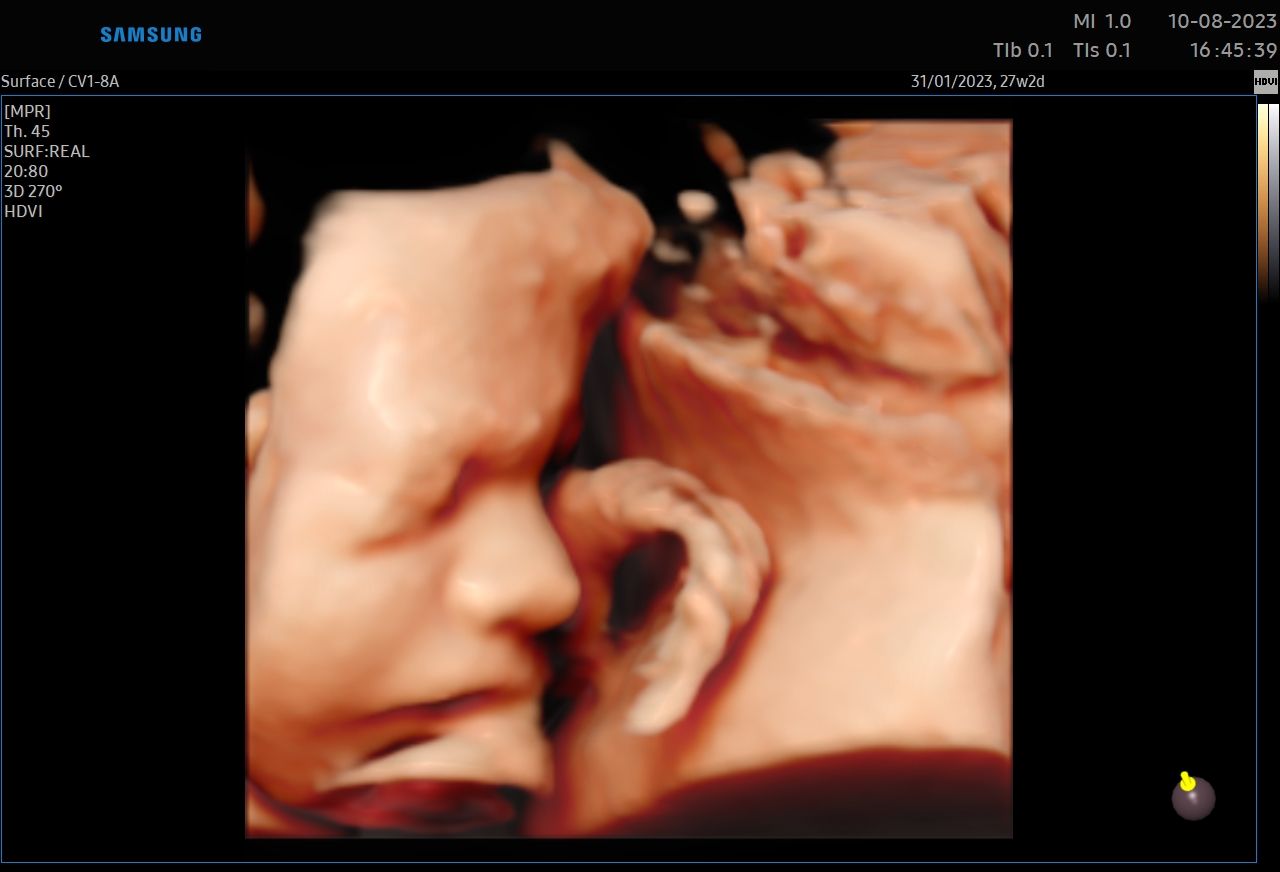

:-) Jestem lekarzem specjalistą w zakresie ginekologii i położnictwa , w ramach prowadzonej praktyki ginekologicznej staram się świadczyć kompleksowe porady lekarskie najwyższym poziomie ,w oparciu o najwyższe standardy jak i przy pomocy najnowszego sprzętu medycznego. W trakcie pracy zawodowej uzyskałem kolejno tytuły specjalisty I stopnia , a później specjalisty II stopnia , a także uzyskałem dodatkowe uprawnienia

CERTYFIKAT BADAŃ PRENATALNYCH POLSKIEGO TOWARZYSTWA GINEKOLOGÓW I POŁOŻNIKÓW

CERTYFIKAT BADAŃ PRENATALNYCH FMF ( FETAL MEDICINE FOUNDATION - LONDYN )

W ramach praktyki wykonuję pełen zakres badań ultrasonograficznych w zakresie ginekologii jak i położnictwa wraz z badaniami prenatalnymi , badaniami ultrasonograficznymi piersi .

Zdjęcia i filmy